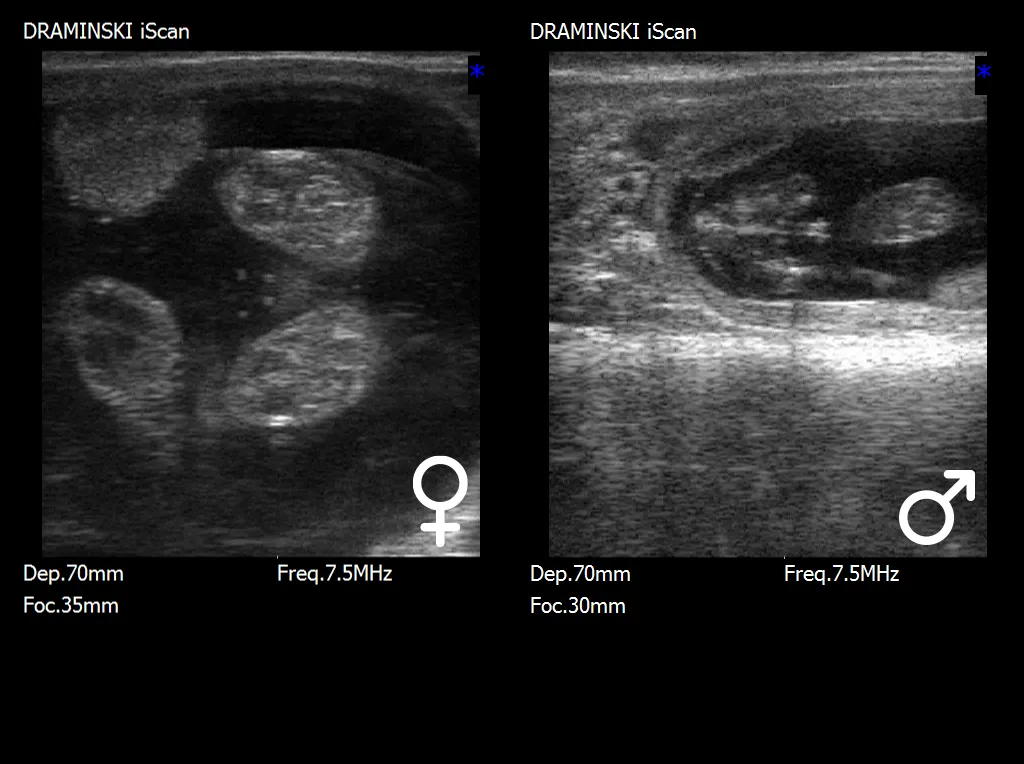

En esta etapa, la estructura diagnóstica clave es el tubérculo genital (tuberculum genitale), que sufre un desplazamiento característico dependiendo del sexo del feto. En los fetos machos, el tubérculo genital se desplaza hacia el ombligo y el futuro pene, mientras que en los fetos hembras, se localiza más cerca de la cola, en la región de la futura vulva. La interpretación correcta de la posición del tubérculo requiere no solo imágenes ecográficas de alta calidad, sino también la experiencia adecuada, ya que pequeñas variaciones en el posicionamiento fetal pueden influir en la evaluación.

En las etapas posteriores de la gestación, después de aproximadamente los días 70–80, se hace posible la identificación de órganos genitales externos más desarrollados, como el escroto en los fetos machos o las estructuras vulvares en los fetos hembras. Aunque las características sexuales son más evidentes en esta etapa, el examen se vuelve más difícil debido al tamaño creciente del feto, su posición más profunda dentro de la cavidad uterina y la maniobrabilidad limitada de la sonda de ultrasonido.